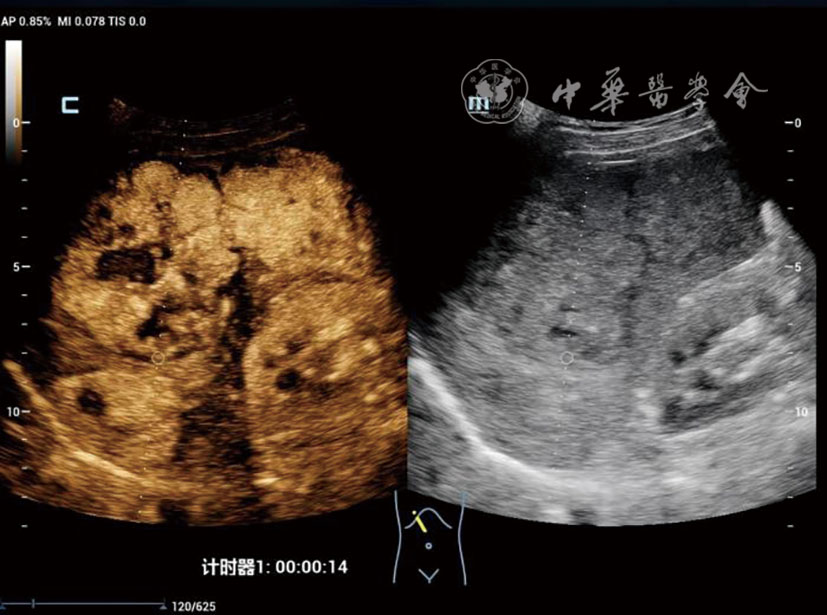

DPHCC组血清甲胎蛋白≥400 ng/ml的比例(48.4% vs 15.0%,P=0.002)及微血管浸润率(77.4% vs 17.5%,P<0.001)显著高于THCC组。超声造影显示,与THCC组相比,DPHCC组动脉期以不均匀增强(38.7% vs 15.0%)和环状增强(16.1% vs 2.5%)为主(P=0.003),且廓清时间更早[(91.94±37.58) s vs (131.65±59.71)s,P=0.002)]。多因素Logistic回归分析显示,肿瘤大小(OR=1.019,P=0.002)、甲胎蛋白≥400 ng/ml(OR=2.798,P=0.032)、边界不清(OR=3.204,P=0.020)及廓清时间<120 s(OR=2.221,P=0.049)是DPHCC的独立危险因素。

The DPHCC group showed significantly higher rates of serum alpha-fetoprotein (AFP) ≥400 ng/ml (48.4% vs 15.0%, P=0.002) and microvascular invasion (77.4% vs 17.5%, P<0.001) compared to THCC. On CEUS, DPHCC predominantly exhibited heterogeneous enhancement (38.7% vs 15.0%) and rim-like enhancement (16.1% vs 2.5%) in the arterial phase (P=0.003), with earlier contrast agent washout initiation (91.94±37.58 s vs 131.65±59.71 s, P=0.002). Multivariate analysis identified tumor size (odds ratio [OR]=1.019, P=0.002), AFP≥400 ng/ml (OR=2.798, P=0.032), ill-defined margin (OR=3.204, P=0.020), and washout time <120 s (OR=2.221, P=0.049) as independent risk factors for DPHCC.

表2 DPHCC组与THCC组患者的灰阶超声及超声造影特征比较[例(%)] |

| 超声特征 | DPHCC组(n=31) | THCC组(n=40) | 统计值 | P值 |

|---|---|---|---|---|

| 内部回声 | χ2=0.25 | 0.883 | ||

| 强回声 | 6(19.4) | 9(22.5) | ||

| 弱回声 | 20(64.5) | 26(65.0) | ||

| 不均匀回声 | 5(16.1) | 5(12.5) | ||

| 边界 | χ2=0.52 | 0.471 | ||

| 清晰 | 20(64.5) | 29(72.5) | ||

| 不清晰 | 11(35.5) | 11(27.5) | ||

| 形态 | χ2=0.67 | 0.413 | ||

| 规则 | 18(58.1) | 27(67.5) | ||

| 不规则 | 13(41.9) | 13(32.5) | ||

增强时间(s,![]() | 15.32±4.37 | 16.88±4.88 | t=1.14 | 0.169 |

廓清时间(s,![]() | 91.94±37.58 | 131.65±59.71 | t=3.41 | 0.002 |

| 动脉期增强方式 | - | 0.003 | ||

| 均匀增强 | 14(45.2) | 33(82.5) | ||

| 不均匀增强 | 12(38.7) | 6(15.0) | ||

| 环状增强 | 5(16.1) | 1(2.5) | ||

| 门脉期增强程度 | - | 0.060 | ||

| 高增强 | 1(3.2) | 4(10.0) | ||

| 等增强 | 4(12.9) | 13(32.5) | ||

| 低增强 | 26(83.9) | 23(57.5) | ||

| 实质期增强程度 | - | 0.157 | ||

| 高增强 | 1(3.2) | 0(0) | ||

| 等增强 | 0(0) | 3(7.5) | ||

| 低增强 | 30(96.8) | 37(92.5) | ||

| 内部灌注缺损 | χ2=0.13 | 0.722 | ||

| 无 | 27(87.1) | 36(90.0) | ||

| 有 | 4(12.9) | 4(10.0) |

注:DPHCC为双表型肝细胞癌;THCC为经典型肝细胞癌;-表示Fisher检验无统计值 |